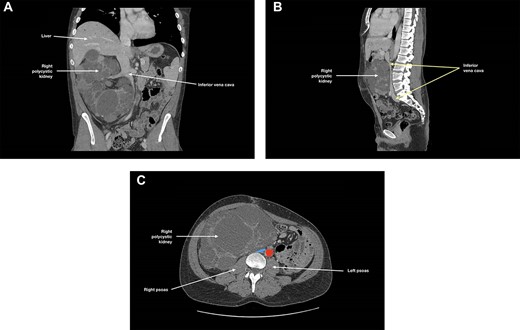

At 3-month follow-up, CT angiogram showed persistent IVC compression by the right polycystic kidney, with near-complete effacement (Fig. 2). There was no thrombus distal to this compression and the patient was asymptomatic. May-Thurner syndrome was ruled out. As the right kidney had been found to cause IVC compression and to extend into the pelvis, an elective right nephrectomy was performed to prevent further thromboses in the right-sided deep venous systems and to create space for subsequent transplantation. The right kidney measured 270 × 170 × 150 mm and weighed 3098 g. There was extensive cystic alteration with fibrosis and tubular atrophy; no malignancy was identified.

(A) Coronal, (B) sagittal and (C) axial views of the patient’s CT angiogram at 3 months post-left nephrectomy, showing persistent inferior vena cava compression by the right polycystic kidney, with near-complete effacement; in (c), the inferior vena cava is depicted in blue and the descending aorta is depicted in red.